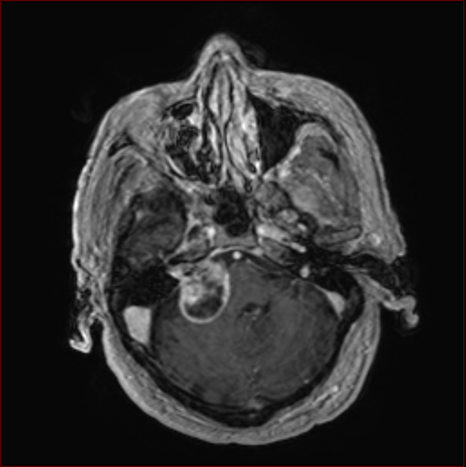

聴神経腫瘍ー術前